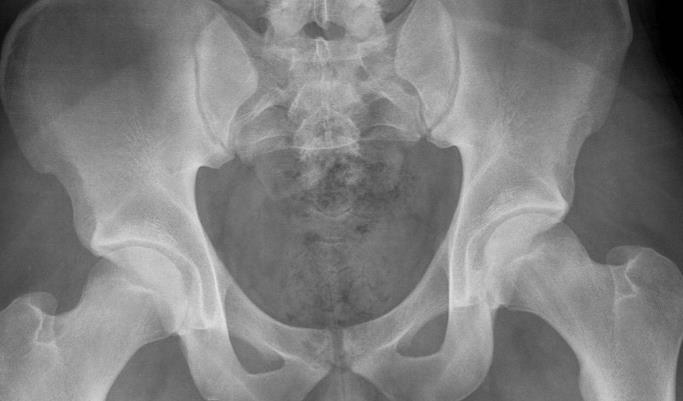

꼬리뼈

꼬리뼈는 미골, 미저골 이라고 부르는데요, 영어로는 coccyx 라고 표기 합니다.